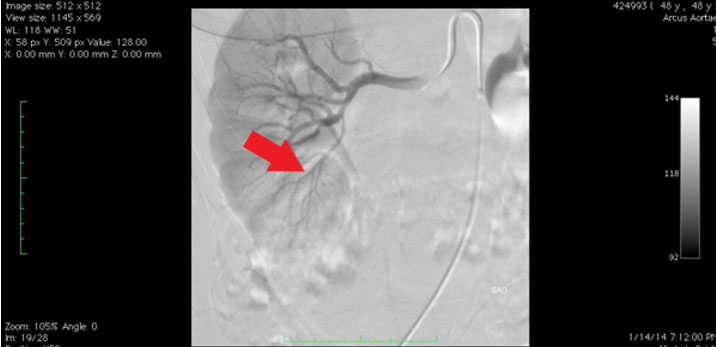

The patient underwent renal angiography two days later. Focal severe stenosis was detected in the polar renal artery at the postero-inferior level (Figure 2). Then, balloon dilatation was performed.

Figure 2: Angiography.

In the past, selective renal arterial angiography was the gold standard for diagnosis. Angiographic classification includes the multifocal type, with multiple stenosis, and the “string-of-beads” appearance that is related to medial FMD, and tubular and focal types, which are not clearly related to specific histological lesions. Today, non-invasive methods such as Doppler sonography, CT scans, and magnetic resonance imaging (MRI) scans are performed [13].